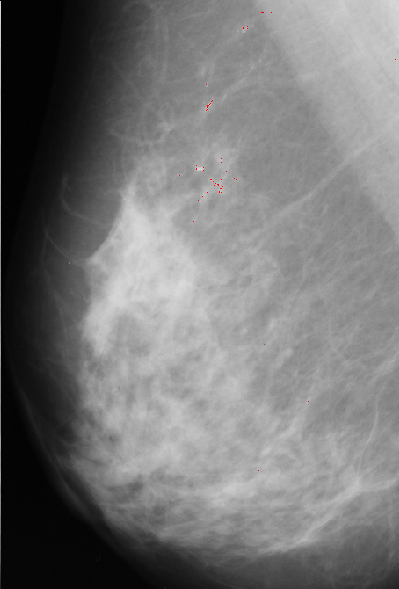

The unsharp filtering only enhances the high-frequency components of the image, thus, has to be followed by a thresholding that will segment the microcalcifications from the breast tissue. This thresholding was done manually and the values for the threshold variable ranged from 170 to 215 in the 4 images.

A result using this approach is presented bellow:

Figure 1.